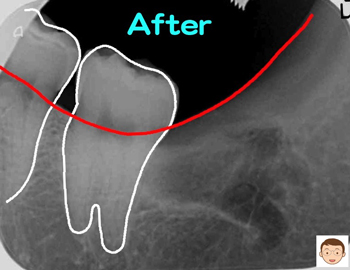

骨の中に埋もれている割合+横向き度合い+根の曲がり具合(左下の写真)→抜歯の難レベル(A→B→C→ウルトラC)から考えると“ウルトラC”に属します。

治療開始から約60分で難しい親知らずの抜歯が終わりました。抜歯跡はテルプラグ(無料)を填入して抜歯後の痛みや腫れを保護します。